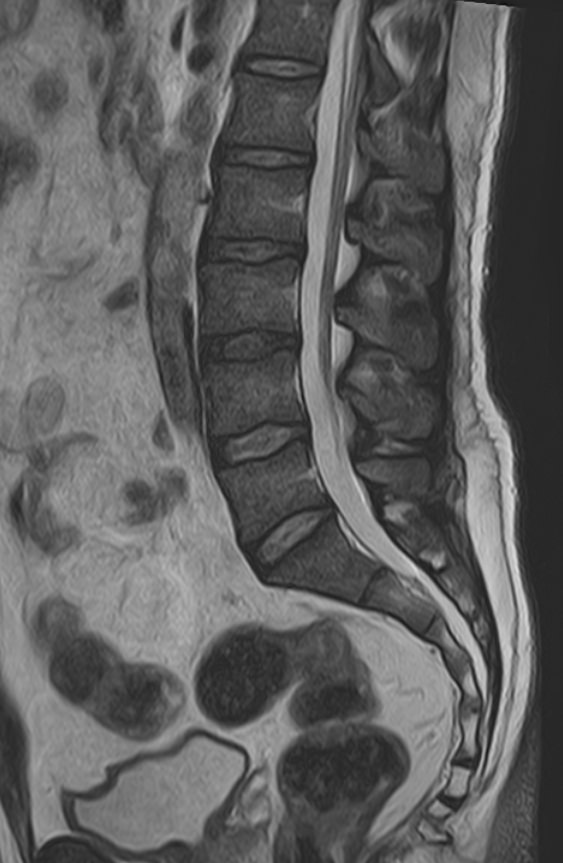

В клинике «Доступная медицина» проводится комплексное обследование позвоночника, включающее два протокола сканирования — МРТ грудного и поясничного отдела.

Магнитно-резонансная томография является наиболее точным и эффективным способом диагностики различной патологии позвоночного столба. Метод позволяет визуализировать не только костные структуры позвонков, но и оценивать состояние спинного мозга на исследуемом уровне, нервных корешков, связочного аппарата и окружающих мягких тканей. МРТ сочетает в себе высокую точность и информативность, при этом является безболезненной, неинвазивной и безопасной процедурой, так как во время исследования не применяется вредное рентгеновское излучение. В основе метода лежит использование магнитного поля, которое не оказывает негативного действия на организм человека.

Комплексное обследование грудного и поясничного отдела позвоночника обычно требуется в тех случаях, когда имеется подозрение на множественное поражение позвоночного столба, которые могут быть вызваны опухолевыми, воспалительными или дегенеративными заболеваниями позвоночника.

Магнитно-резонансная томография, предусматривающая обследование средней и нижней части спины, охватывает область семнадцати позвонков: двенадцать из них формируют заднюю стенку грудной клетки, пять находятся между ребрами и крестцовым отделом. Исследование позволяет визуализировать:

МРТ грудо-поясничного отдела позвоночника обладает высокой чувствительностью и специфичностью. Она позволяет не только определять границы патологических очагов, но и решает более сложные диагностические задачи. МР-сканирование является обоснованным методом выбора при врожденных аномалиях развития, синдроме фасеточных суставов, межпозвонковых грыжах, остеомиелите, заболеваниях спинного мозга, вертебральных опухолях.